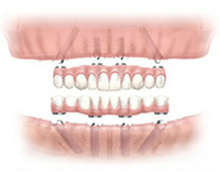

オールオンフォー(All-on-4)

All-on-4(オールオンフォー)は、歯をすべて失った患者様にインプラントの埋入手術を行い、その日のうちに仮義歯にしっかり固定することで、手術当日から食事も可能になるという画期的なインプラント治療法です。

このオールオン4は、インプラント治療のデメリットといわれる「治療期間」「経済性」「審美性」「外科的侵襲」など患者様にとってのあらゆる負担を軽減した、まったく新しいコンセプトの治療法です。